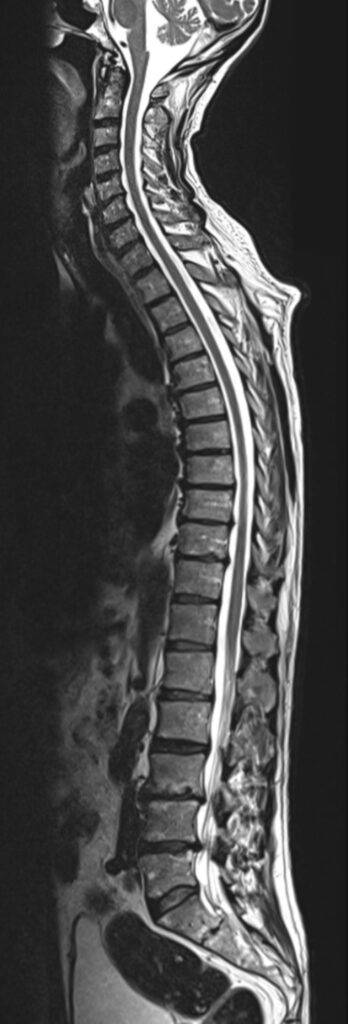

Die MRT Rücken Untersuchung gliedert sich in drei Hauptabschnitte und ermöglicht eine ganzheitliche Darstellung der Wirbelsäule. Die Wirbelsäule ist ein komplexes Konstrukt im Körperinneren und lässt sich durch eine Magnetresonanztomographie anhand MRT Bildern präzise darstellen.

Der Rücken kann bei einer MRT in Abschnitten untersucht werden:

- Halswirbelsäule (HWS)

- Brustwirbelsäule (BWS)

- Lendenwirbelsäule (LWS)

Es ist ebenfalls möglich, bei einer MRT Wirbelsäule die gesamte Wirbelsäule darzustellen.

Bei einer Wirbelsäule MRT können sowohl knöcherne Strukturen als auch Weichteile erkannt und folglich untersucht werden. Dadurch eignet sich die MRT Wirbelsäule besonders gut, um Schmerzen mit unklarer Ursache im Rücken und der Wirbelsäule abzuklären. Denn auf den MRT-Bildern des Rückens können Schäden an der Wirbelsäule, den Bandscheiben und am Rückenmark erfasst werden.